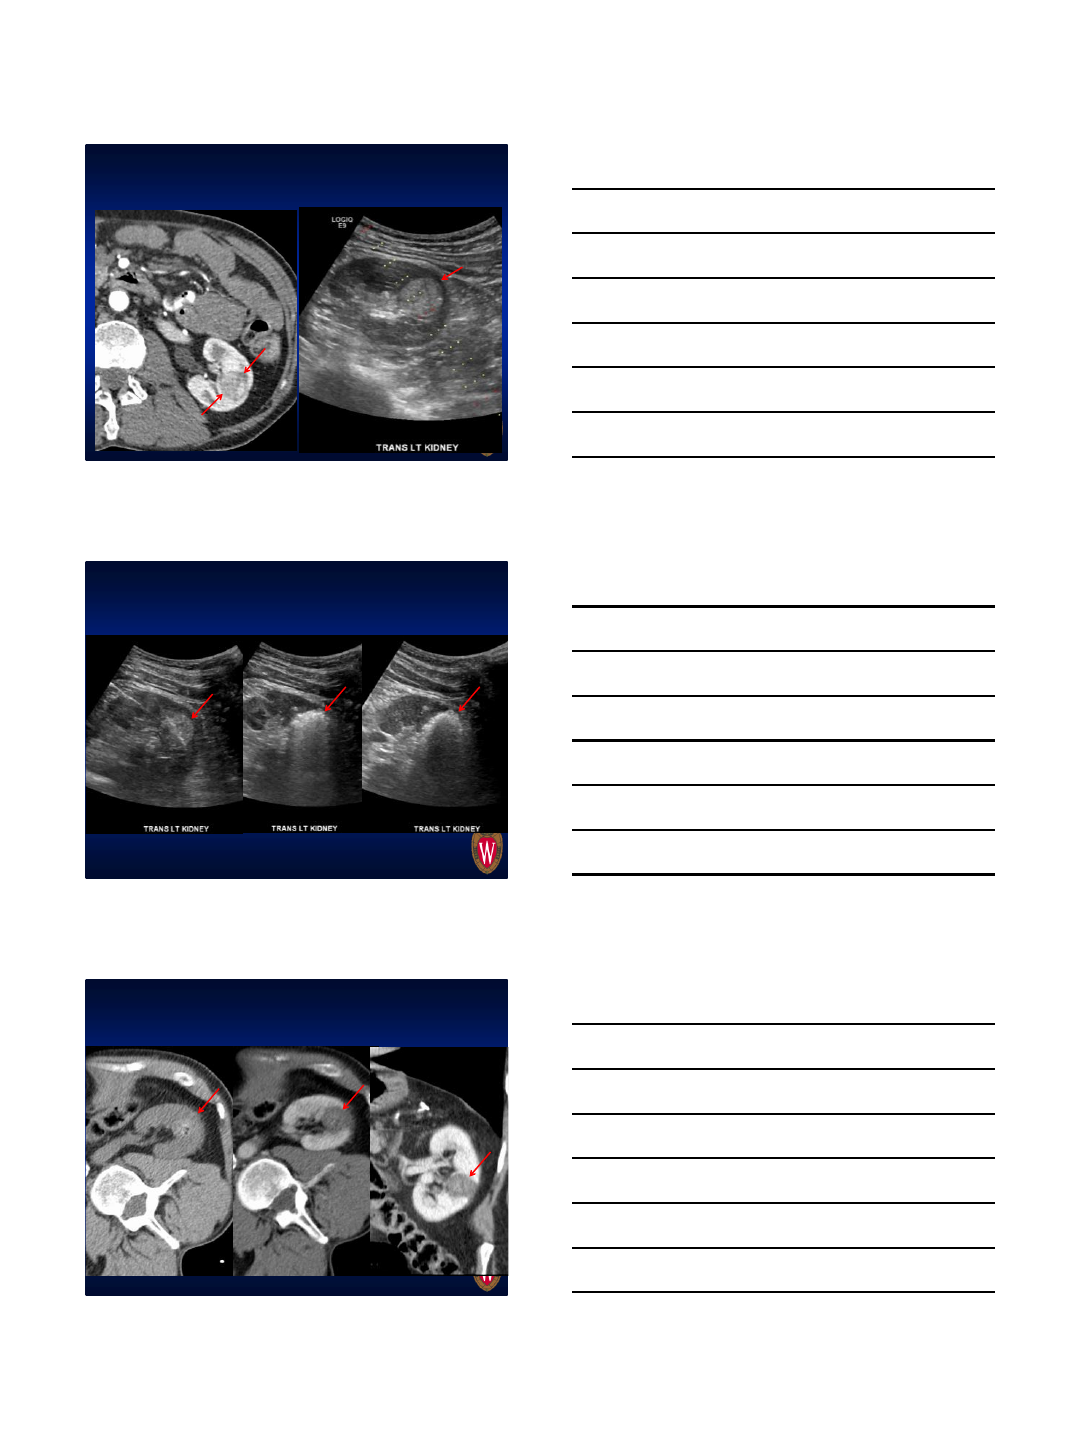

How we place probes now

2.2 cm endophytic RCC

2PR’s, 65W for 3 minutes, then 40W for 2

minutes

During ablation (bubbles highly visible)

Post ablation CT